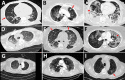

Aspergillosis complicating severe influenza infection has been increasingly detected worldwide. Recently, coronavirus disease-associated pulmonary aspergillosis (CAPA) has been detected through rapid reports, primarily from centers in Europe. We provide a case series of CAPA, adding 20 cases to the literature, with review of pathophysiology, diagnosis, and outcomes. The syndromes of pulmonary aspergillosis complicating severe viral infections are distinct from classic invasive aspergillosis, which is recognized most frequently in persons with neutropenia and in other immunocompromised persons. Combined with severe viral infection, aspergillosis comprises a constellation of airway-invasive and angio-invasive disease and results in risks associated with poor airway fungus clearance and killing, including virus- or inflammation-associated epithelial damage, systemic immunosuppression, and underlying lung disease. Radiologic abnormalities can vary, reflecting different pathologies. Prospective studies reporting poor outcomes in CAPA patients underscore the urgent need for strategies to improve diagnosis, prevention, and therapy.